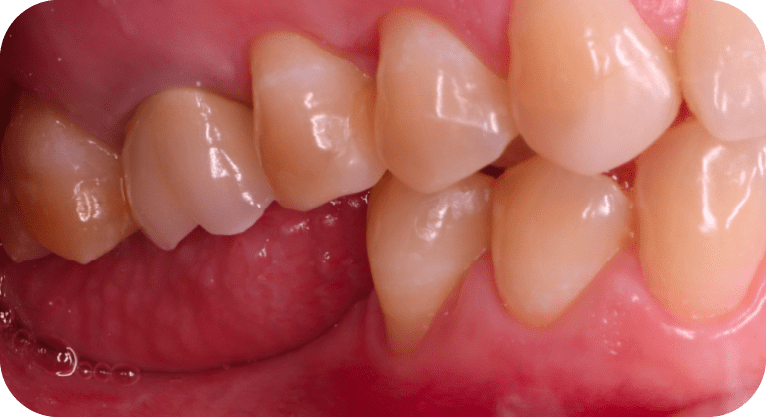

Female patient, “42” years old

Treatment: Dental implant

The patient came to the clinic aer losing two molars due to advanced decay, which affected her chewing function. To restore the edentulous area, dental implants were placed in the corresponding spaces, restoring chewing ability, preventing bone loss, and maintaining the alignment of adjacent teeth, achieving satisfactory functional and aesthetic results.